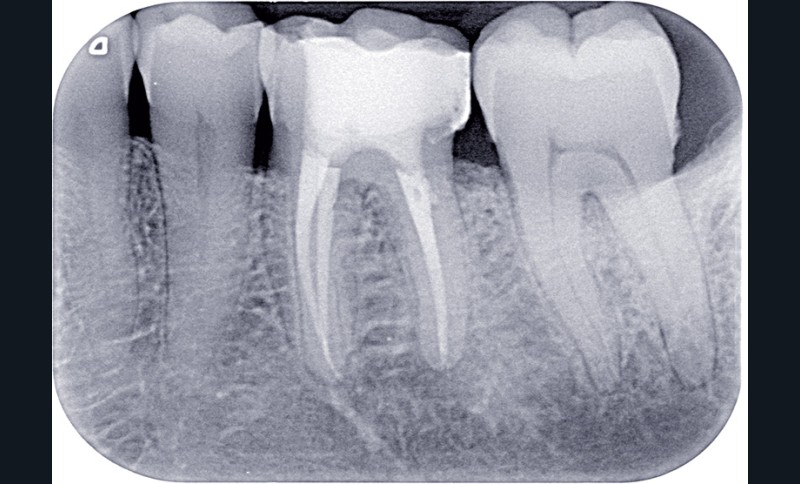

Dans ces situations, le praticien est conduit à dépulper et à restaurer les dents traitées endodontiquement. Les traitements doivent alors s’inscrire dans le concept du continuum endo-restaurateur qui a été défini comme étant « le processus spatio-temporel sans interruption ni rupture qui débute par l’accès à l’endodonte et s’achève avec la mise en place de la restauration prothétique d’usage » (1). Il existe bien une continuité, du traitement endodontique à la restauration fonctionnelle d’usage qui conditionne le pronostic et les résultats du traitement à long terme (fig. 2).

L’OBTURATION CANALAIRE

L’obturation tridimensionnelle canalaire permet de maintenir l’état de désinfection obtenu lors de la préparation chimiomécanique. C’est l’obturation complète de l’ensemble du réseau canalaire, aussi près que possible de la jonction cémentodentinaire. Elle fait partie intégrante de la triade endodontique dont les deux autres composantes sont la mise en forme et l’irrigation. Le praticien est amené à se poser la question suivante : quelle technique d’obturation choisir ? La vraie problématique réside dans la mise en forme. En effet, un canal mal mis en forme sera mal nettoyé et par conséquent mal obturé. Ainsi, les différents…